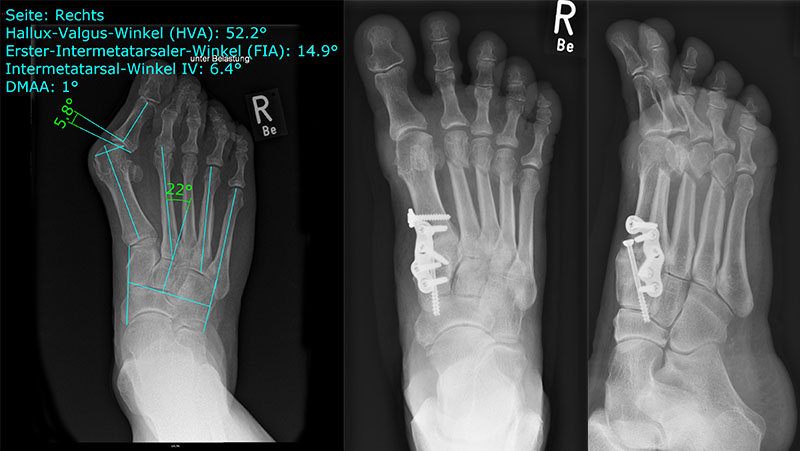

• Folgende Winkel können präoperativ zur Erleichterung der Planung am Röntgenbild eingezeichnet werden:

• IMW (Intermetatarsalwinkel).

• HVW (Hallux valgus-Winkel).

• DMAA (Distal Metatarsal Articular Angle) – Planung der ggf. notwendigen Reverdin-Isham-Osteotomie.

• PPAA (Proximal Phalangeal Articular Angle) – Planung der ggf. notwendigen Akin-Osteotomie.

• VAW (Vorfußadduktionswinkel) – Planung der Ausrichtung der DMMO (Distalen minimalinvasiven Metatarsale Osteotomien).

Einschränkend ist anzumerken, dass o.g. Winkel projektions- und rotationsabhängig sind 15. Daher ist intraoperativ die Planung anhand von Bildverstärkeraufnahmen zu verifizieren und ggf. anzupassen.

In unserer prospektiven Studie wurden 10 Patienten (8 Frauen und 2 Männer; Ø Alter 58 ¼ Jahre) mit einem symptomatischen Hallux valgus bei Pes adductus und Metatarsalgie mittels einer Lapidusarthrodese und einer lateralisierenden DMMO versorgt. Die Fusion des TMT-I-Gelenkes erfolgte offen mittels einer winkelstabilen, plantaren Platte. Alle zusätzlichen distalen Eingriffe (DMMO, Isham-OT, Akin-OT, Kleinzehenkorrekturen) wurden in minimalinvasiver Technik durchgeführt. Die Patienten wurden nach 6 Monaten klinisch und radiologisch nachuntersucht.

Der präoperative AOFAS-Score betrug 41,5 Punkte und konnte postoperativ auf durchschnittlich 86,2 Punkte verbessert werden (p<0,005). Der IMW reduzierte sich von Ø 16,7° (8,5°-20,3°) präoperativ auf Ø 7,14° (6,1°-9,5°) (p<0,005). Ebenso konnte der HVW von präoperativ Ø 45,2° auf postoperativ Ø 9,4° (p<0,005) korrigiert werden. Durch die Durchführung der modifizierten, lateralisierenden DMMO veränderte sich der präoperative VAW von Ø 23° (19,3°-33,5°) auf Ø 15,6° (13°-17,2°; p<0,004).